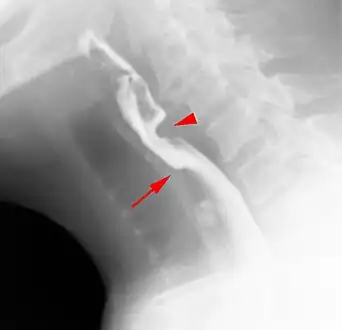

Esophageal webs are thin membranes occurring anywhere along the esophagus.[1]

Esophageal webs are thin 2–3 mm (0.08–0.12 in) membranes of normal esophageal tissue consisting of mucosa and submucosa that can partially protrude/obstruct the esophagus. They can be congenital or acquired. Congenital webs commonly appear in the middle and inferior third of the esophagus, and they are more likely to be circumferential with a central or eccentric orifice. Acquired webs are much more common than congenital webs and typically appear in the cervical area (postcricoid).

The diagnostic test of choice is a barium swallow.